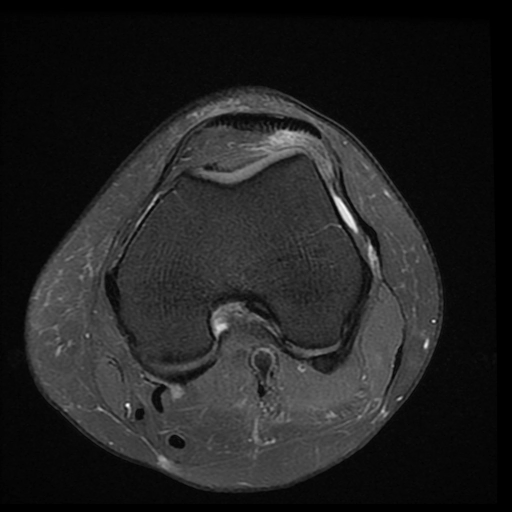

Hội chứng chèn ép túi mỡ Hoffa (Hoffa fat pad impingement syndrome)